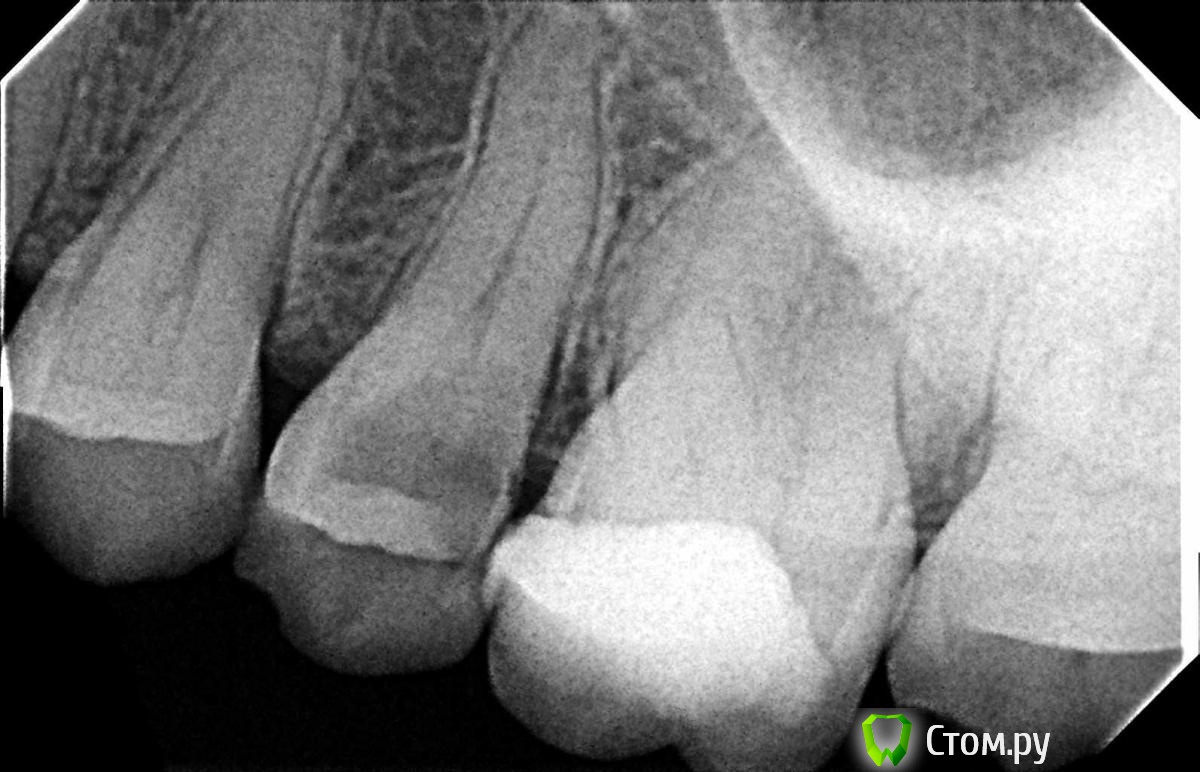

Hans85 Опубликовано 8 января, 2014 Автор Поделиться Опубликовано 8 января, 2014 НУ еще чуток доступа может кому будет интересноПациент - геморная кариозная полость по дистальной поверхности 47,точка сообщения с полостью зуба обнаружилась,традиционный доступ уничтожил бы зуб,пришлось хитрить. 11 Ссылка на комментарий